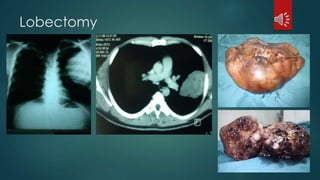

 Lobectomy

Lobectomy